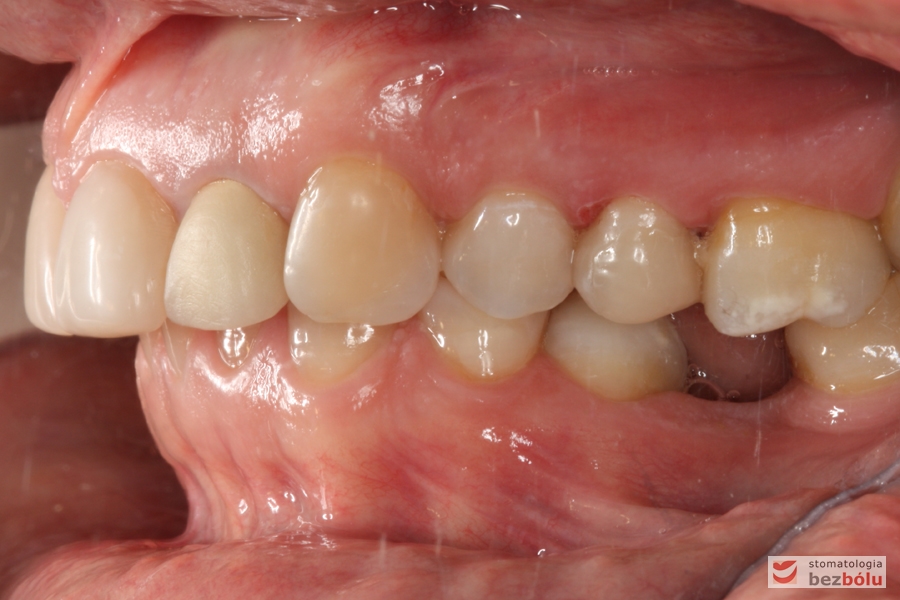

Zęby w zgryzie - strona prawa, II klasa kłowa i Angle'a, mezjalna inklinacja kła

Zęby w zgryzie – strona prawa, II klasa kłowa i Angle’a, mezjalna inklinacja kła